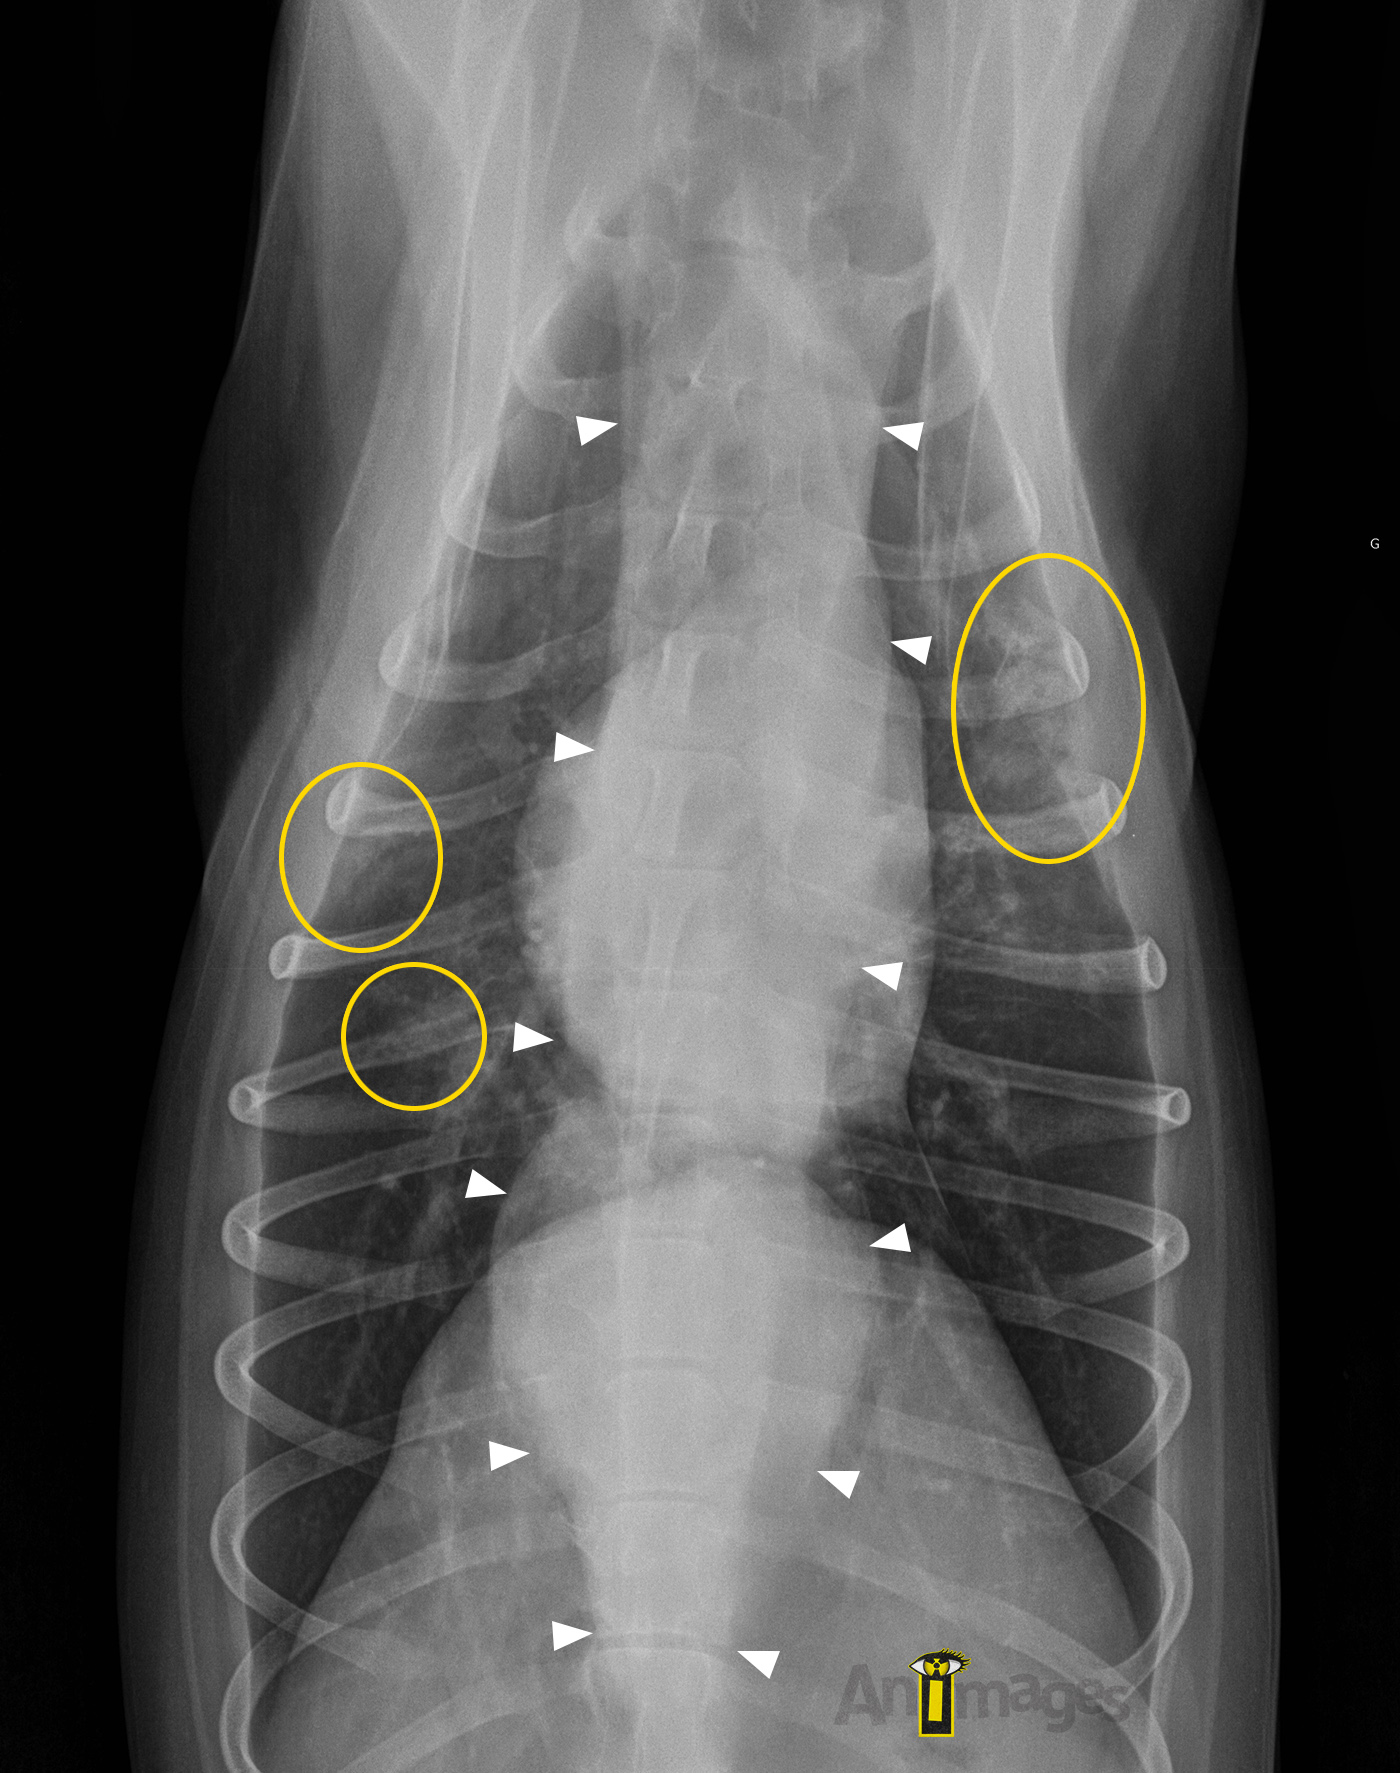

Dorsoventrale